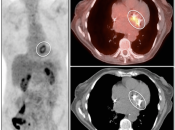

Value of Non-Attenuation Corrected (NAC) Images

Resolving Attenuation Correction Artifacts:

The CT images obtained during an exam are not only used for “anatomic” interpretation. They are also used for “attenuation correction” (AC) of the PET images, generating the much more useful AC PET images used for interpretation.

Unfortunately, attenuation correction of PET images can result in falsely elevated metabolic activity in regions of high CT density (e.g. metallic devices, oral contrast, calcification).

In such cases, these areas must be reviewed on the NAC (non-attenuation correction) images. If these regions are not also hypermetabolic on the NAC images, then their apparent increased FDG-uptake on the AC images is artefactual.

This phenomenon is almost exclusively seen with older PET/CT scanners, as most modern scanners utilize newer algorithms that do not “over-correct” in these areas of increased density.

Lung Nodule Identification:

NAC images can occasionally be useful in identifying mild to moderately FDG-avid lung nodules, especially those located in the lung periphery or lung bases.